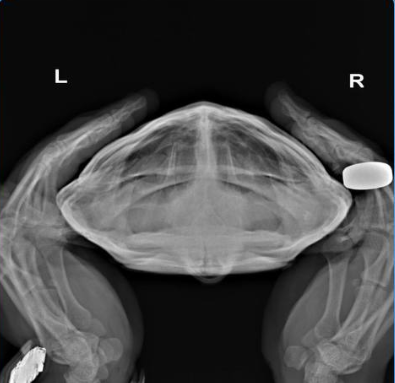

тут только рентген делать и смотреть нет ли инородных тел внутри.

@NovoEvg вообще рентген можно сделать в любой ветклинике с рентгеном. Я могу дать настройки аппарата и если что - можно взять онлайн консультацию у нашего герпетолога.

Если самка пытается вылезти из аквариума - есть вероятность, что там могут быть яйца. Они тоже могут вызывать срыгивание пищи, т.к. давят на внутренние органы. Яйца хорошо будут видны на рентгене и для этого не нужно быть специалистом, чтобы их увидеть. Снимок просто лежа на животе.

Также это могут быть увеличенные фолликулы - когда процесс формирования яиц не завершается, а они потом обратно "сдуваются", но это на рентгене не увидеть, тут уже нужно узи и специалист.

@NovoEvg в идеале нужно сделать 3 проекции

но если по деньгам туго, то одну - лежа на животе

настройки 67кВ на 2мА/сек

Также допустимо 50кВ на 6-8мА/сек